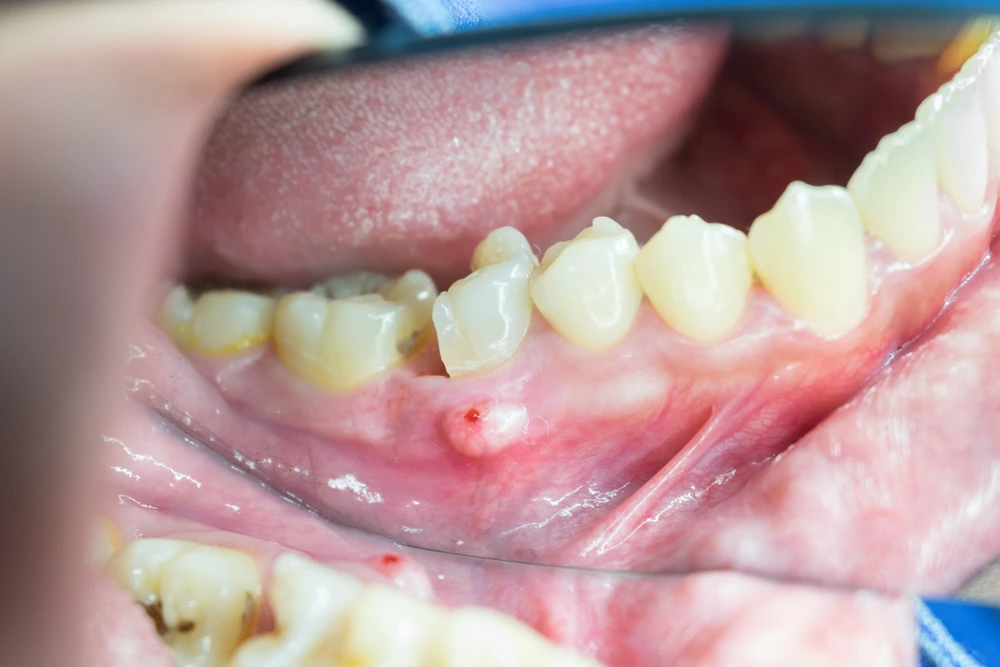

Masalah pada akar gigi sering kali disebabkan oleh infeksi yang berasal dari gigi berlubang atau gigi yang sarafnya sudah mati. Infeksi ini bisa berkembang menjadi

Gigi berlubang (dental caries) terjadi akibat proses de-mineralisasi enamel dan dentin oleh asam yang diproduksi bakteri, terutama Streptococcus mutans dan Lactobacillus. Ketika lubang semakin dalam, kerusakan mencapai lapisan dentin dan akhirnya pulpa, tempat